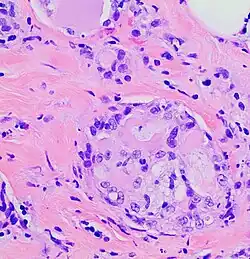

The microscopic histopathology of H&E-stained MSC tumors generally shows well-circumscribed solid tumors with multiple microcysts[13] and sheets of epithelial cells containing numerous vacuoles in their cytoplasm, signet ring cells (i.e. cells with one large cytoplasmic vacuole termed a globule), and extracellular droplet-like secretions resembling the cytoplasmic globules.[2] The sheets of cells are separated by bands of connective tissue.[5] In occasional cases, the cells in MSC tumors are arranged in a papillary (i.e. finger-like)[17] or tubular[14] pattern. The extracellular microcysts and intracellular vacuoles and globules stain red when stained with the H&E stain, consist of sulfated glycosaminoglycans and mucin-containing material,[4] and are identified using periodic acid-Shiff, PAD diastase, or Alician blue stains.[15] The term “secretory” for MSC is in recognition that the tumor cells vacuoles and globules are secreted extracellularly to give the tissues their microcystic appearance.[8] At least 2 cases of MSC had sarcoma-like malignant cells in portions of their tumors and a rapidly metastasizing disease.[18][19]